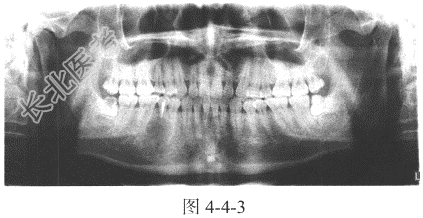

- [材料题] 患者,男,28岁,下颌部疼痛3天,查体:外形无异常,可触及一小结节状突起(图4-4-3)。

- 简答题1、患者X线检查的主要影像表现是什么?

- 简答题2、综合上述病史,应考虑何种疾病?如何确诊?